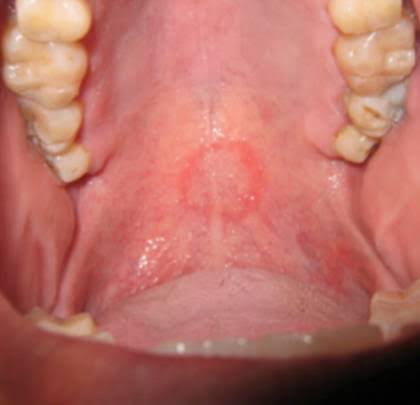

สำหรับคนที่สงสัย เวลามี oral sex จะเป็นรอยกลมๆแบบนี้ หมอฟันเห็นกันเป็นปกติ(โดยเฉพาะหลังวันวาเลนไทน์) รอยจะหายไปเองใน1อาทิตย์จ้า